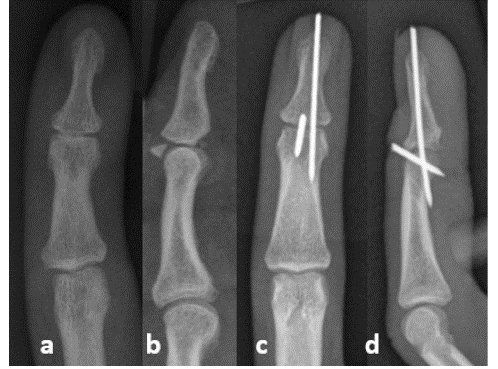

Хирургические методы лечения молоткообразного пальца с непроходимостью и фиксацией спицами Киршнера

Молотчатый палец возникает в результате сгибания или переразгибания вытянутой дистальной фаланги с отрывом кости в м···